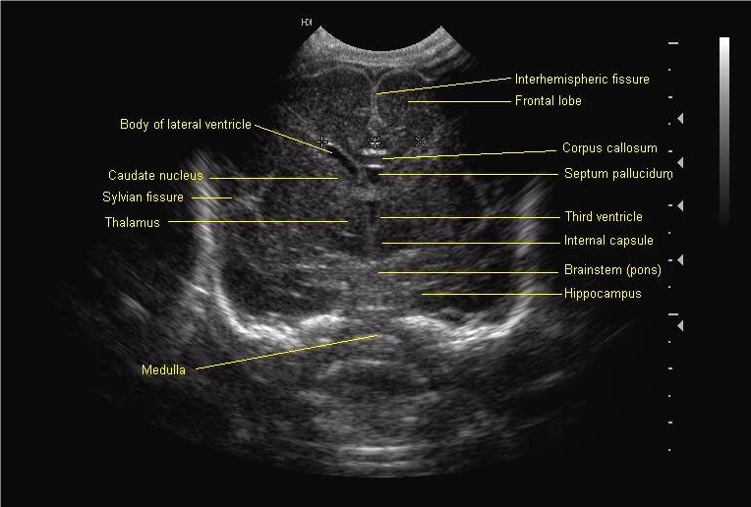

All scan results should be discussed with parents and, unless normal, this should be done by a member of the senior medical team. Although standard views for examination and hard copy print out are shown below, it is good practice to examine the peripheries of the brain including extreme lateral sagittal views, extreme anterior and posterior coronal views.

Mid Coronal